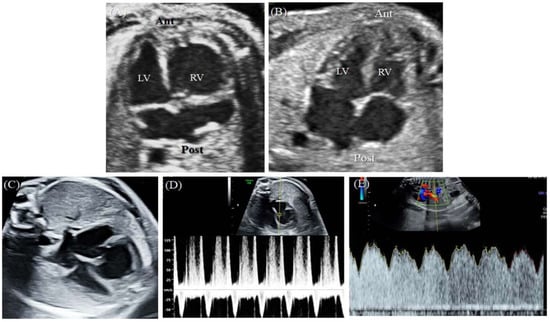

A 43-year-old pregnant woman with dichorionic diamniotic (DCDA) twins was referred due to abnormal fetal ultrasonographic findings for one of the twins. At a gestational age (GA) 26+2 weeks, fetal echocardiography of the upper fetus showed an enlarged and globular right ventricle (RV) with midsystolic tricuspid regurgitation (TR) when compared with the findings for the lower fetus (Figure 1A,B). Except for the ventricular differences and TR, the cardiac structures of the upper fetus were normal, and there were no associated abnormalities. In early pregnancy, the mother underwent genetic amniocentesis because of her advanced age, and the karyotypes of both fetuses were normal. Additionally, the detailed sonographic findings of the lower fetus were normal. At a GA of 30+5 weeks, the globular shape of the RV remained unchanged, but holosystolic TR was observed (Figure 1C,D). Since there was a risk of fetal hydrops or demise due to the progression of TR, Doppler testing, including the ductus venosus, was performed, and the results were normal (Figure 1E).

Cardiac function parameters were computed by FetalHQ with STIC volume acquisition, and the results are shown in Table 2 and Figure 5. The ejection fraction (EF) of the fetus with CVD decreased from 46% at a GA 33+5 weeks to 42% at a GA 35+2 weeks, whereas the EF of the healthy fetus was 46% at a GA of 35+2 weeks. The global longitudinal strain (GLS) in the RV of the fetus with CVD decreased from −6.43% to −4.97%, while the LV GLS increased from −2.96% to −5.53%. Regardless of the ventricle, the GLS of the fetus with CVD was lower than that of the healthy fetus (Table 2).

Figure 1. This is a figure. Schemes follow the same formatting.(A) At 26+2 weeks GA, the upper fetus showed globular RV enlargement compared with (B) the lower fetus, who had a normal heart. (C) At 30+5 weeks GA, the globular shape of the RV remained unchanged, but (D) holosystolic TR was observed. (E) Doppler evaluation of the ductus venosus showed normal findings. Ant, anterior; Lt, left; LV, left ventricle; Post, posterior; Rt, right; RV, right ventricle.